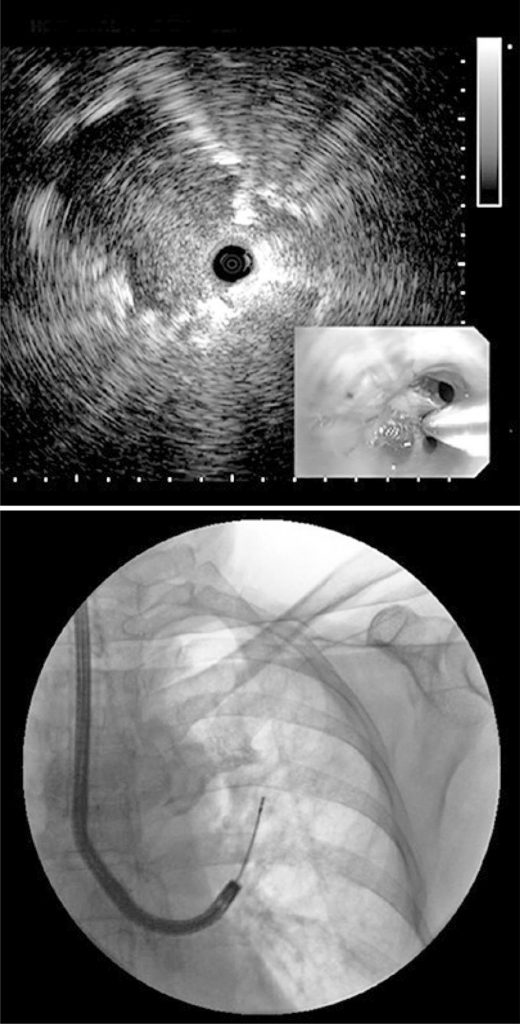

Figure 5

Radial endobronchial ultrasound and transbronchial biopsy guided by fluoroscopy